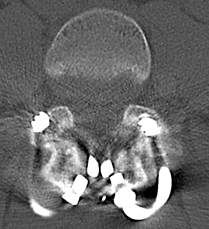

胸椎黄色靱帯骨化症を認め脊髄を圧迫している状態です。骨化部分を切除することで脊髄の圧迫を解除し症状は改善しています。